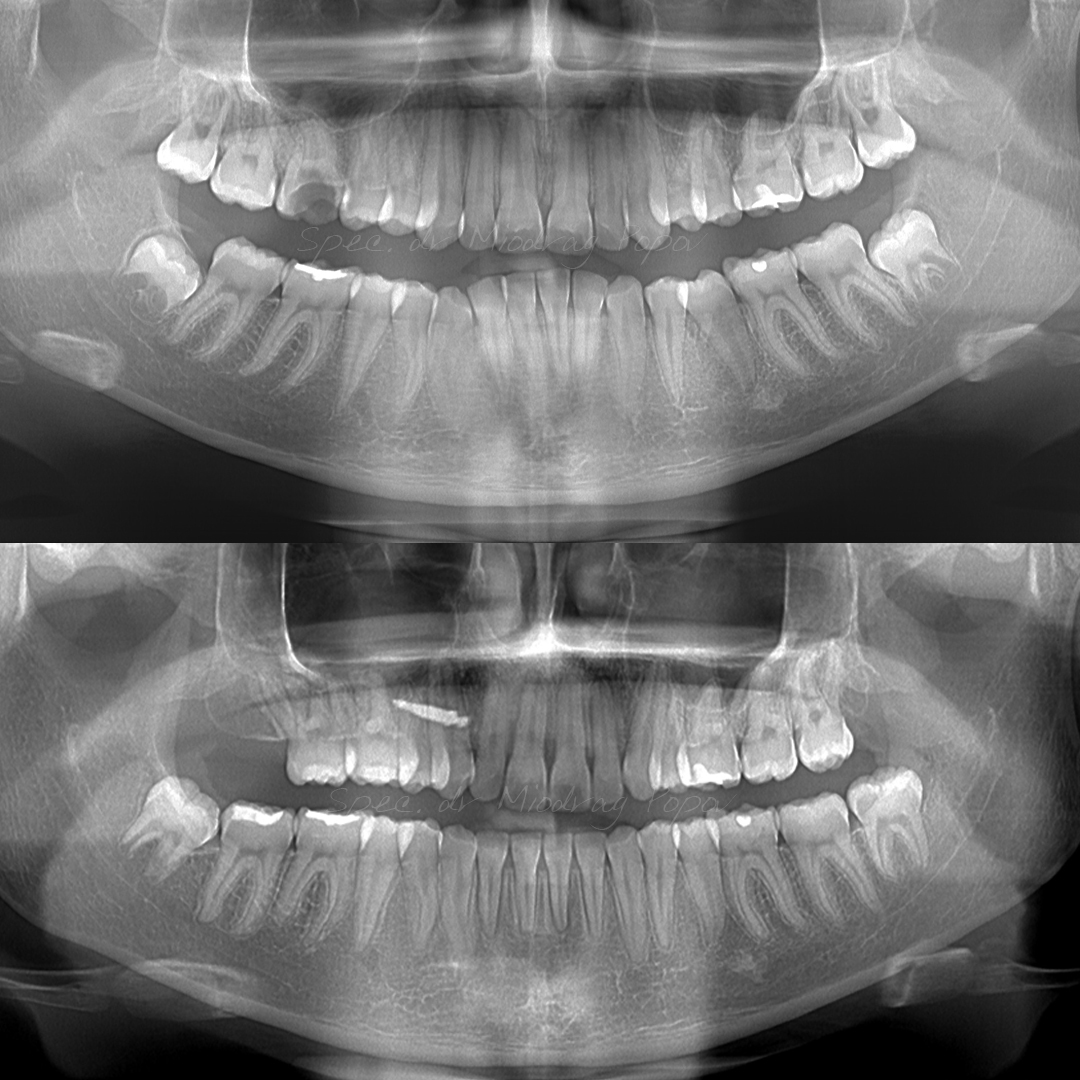

Slučaj ortodontske terapije II klase s vađenjem gornjih prvih predkutnjaka.

Na početku terapije, pacijentkinja je već imala izvađen gornji prvi kutnjak.

Tokom tretmana, svi prostori su zatvoreni, a profil lica transformisan.